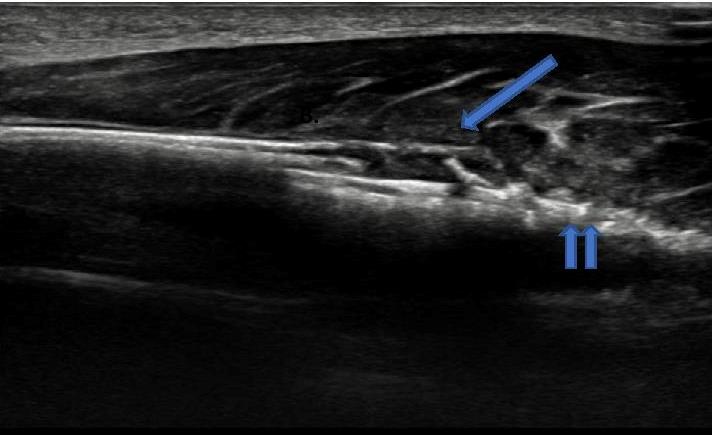

![]() |

Image B : Longitudinal image of dorsal aspect of proximal right ulna : demonstrates a soft tissue mass (arrowed) elevating the periosteum at the margin of an area of permeative cortical destruction (double arrow). |